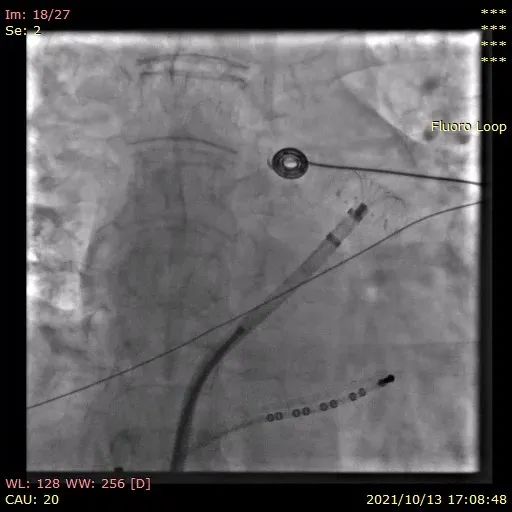

综合考虑以上2种型号的利弊和心耳的实际情况,李岳春教授选择LAmbre™2430封堵器并采用 “推送式”植入法打开封堵器,口部半打开固定盘,整体推送到达理想区域后再完全展开固定盘。切线位观察固定盘U型钩与连接件位于同一直线上,且受力均匀,形态良好。

图4:固定盘口部半展开

图5:推送固定盘到理想区域后完全打开